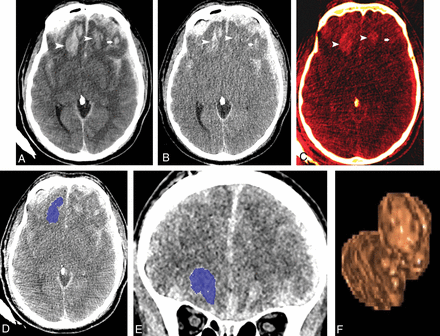

There is increasing availability of dual-energy CT (DECT) technology in major academic and level 1 trauma centers. We have included a high-monochromatic (190-keV) image set in our routine head CT protocol at the University of Maryland Shock Trauma Center and Adult Emergency Department due to its potential to positively affect the display of cortical contusions and subdural hematomas by decreasing the beam-hardening artifacts from cranial bones.9⇓–11 Mixed 120-kV images derived from dual-energy data mirror typical single-energy CT (SECT) images used in clinical practice. We have frequently observed higher hemorrhagic contusion volumes on follow-up 120-kV compared with 190-keV images (Fig 1A, -B). This discrepancy was seen in patients after admission contrast-enhanced whole-body CT (WBCT) imaging, which has become a widely used technique for the work-up of the patient with blunt polytrauma.12

A 55-year-old man with traumatic brain injury sustained after an assault. A, Follow-up axial 120-kV image shows hemorrhagic contusions in both frontal lobes (arrowheads and arrow). B, Virtual high-monochromatic image (190-keV) shows significantly smaller hemorrhagic contusions compared with the 120-kV images due to negligible attenuation contribution from leaked iodinated contrast (arrowheads and arrow). C, Iodine overlay image shows contrast staining of the hemorrhagic contusions (arrowheads and arrow). Axial (D) and coronal (E) CT images demonstrate the ROIs drawn by 3D segmentation on the thin-client server. F, Segmented volume-rendered image of the hemorrhagic contusion.

Studies have shown an increase in capillary endothelial permeability in contusions and surrounding parenchyma.2 We hypothesized that the discrepancy in measured volumes on follow-up noncontrast head CT is caused by retained iodinated contrast that leaks into the parenchyma through the permeable endothelium in the epicenter and penumbra of the contusions after admission contrast-enhanced WBCT (Fig 1C). The high attenuation of the leaked iodine resembles that of hematoma on 120-kV images, resulting in volume overestimation.13⇓–15 The linear attenuation of iodine shows a dramatic decrease along the spectrum of monochromatic energy, therefore greatly reducing the attenuation contribution of iodine at 190 keV, while at the same time, maintaining the attenuation of hematoma relatively constant.16,17 Hence, at clinically relevant tissue iodine concentrations, the attenuation contribution of iodine tends to be negligible at 190 keV and demonstrates only the attenuation resulting from hematoma, thus allowing true measurement of hematoma volume.13,16,17 This phenomenon needs to be substantiated in a systematic study. We aimed to retrospectively determine HPC rates on 120-kV and 190-keV images derived from DECT data and the magnitude of hematoma volume overestimation on follow-up 120-kV images in patients after admission contrast-enhanced WBCT.

DECT data from admission and follow-up head CTs were processed to derive 190-keV image sets at 5-mm slice thickness and 5-mm intervals on a workstation (syngo.via, Version VB10B; Siemens) and sent to the PACS. Both 120-kV and 190-keV image sets from the PACS (5-mm slice thickness, 5-mm intervals) were loaded onto the thin-client server at our institution (IntelliSpace Portal; Philips Healthcare, Best, the Netherlands) to facilitate hematoma volume measurements. Hence, 4 image sets were used for volume measurements in each patient (ie, 120-kV, 190-keV image sets [from the admission study] and 120-kV, 190-keV [from the follow-up study]). Reviewer 1 annotated the hemorrhagic contusions that were meant for volume measurements. In patients with multiple contusions, the largest lesion was used for measurement. Reviewer 2 (third-year radiology resident) measured the volumes of the hemorrhagic contusions in each patient. Measurements were randomly performed regarding patient order and the order of the image sets to avoid potential preconceived bias. Volumes were measured using semiautomated 3D segmentation. An ROI was drawn on axial slices with the use of coronal and sagittal slices to exclude unwanted surrounding brain tissue from the ROIs (Fig 1D–F).19